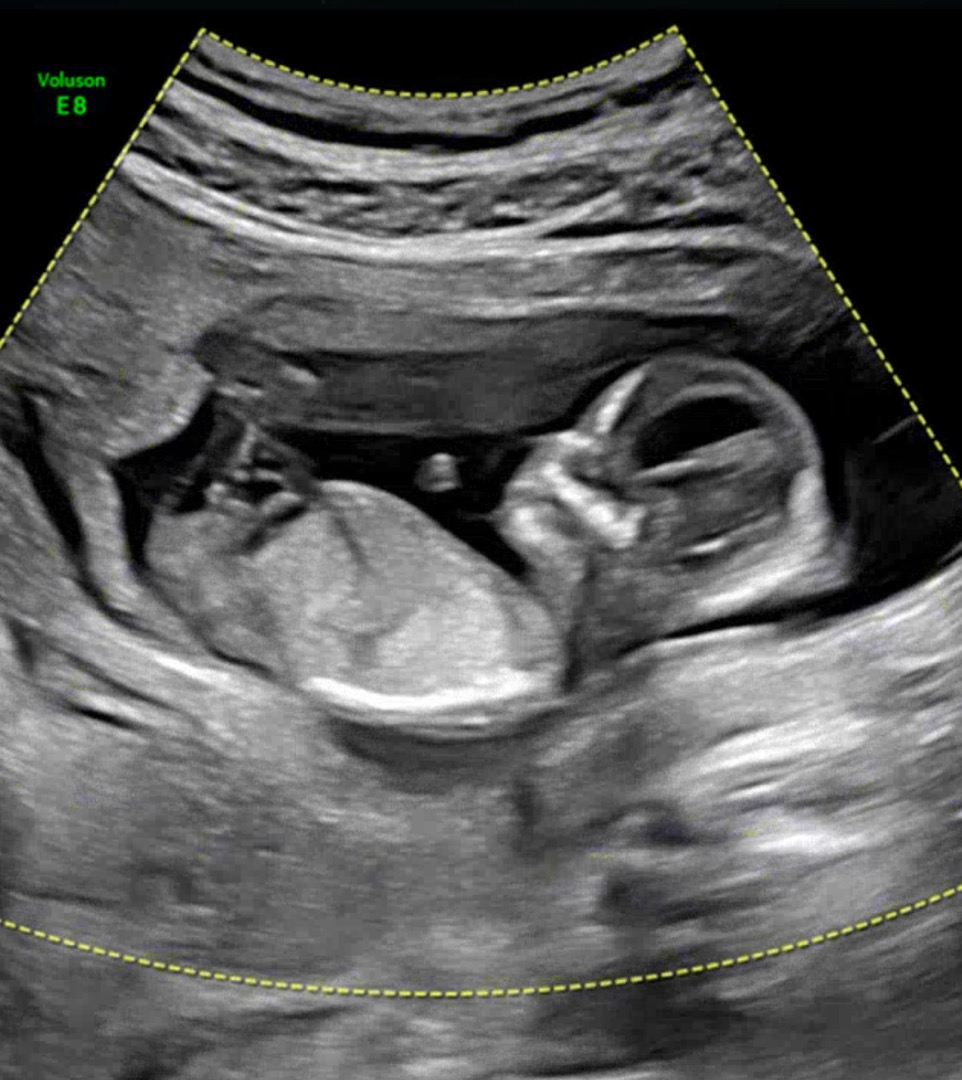

12주 5일차 1치기형아 검사했어용 목투명대 1.5mm괜찮겠죠? 각도법도 참견해주세요